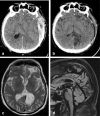

Background and purpose: The splenium of the corpus callosum is the most posterior part of the corpus callosum. Its embryological development, anatomy, vascularization, function, imaging of pathology, possible pathophysiological mechanisms by which pathology may develop and the clinical consequences are discussed.

Methods: A literature-based description is provided on development, anatomy and function. MR and CT images are used to demonstrate pathology. The majority of pathology, known to affect the splenium, and the clinical effects are described in three subsections: (A) limited to the splenium, with elaboration on pathophysiology of reversible splenial lesions, (B) pathology in the cerebral white matter extending into or deriving from the splenium, with special emphasis on tumors, and (C) splenial involvement in generalized conditions affecting the entire brain, with a hypothesis for pathophysiological mechanisms for the different diseases.

Results: The development of the splenium is preceded by the formation of the hippocampal commissure. It is bordered by the falx and the tentorium and is perfused by the anterior and posterior circulation. It contains different caliber axonal fibers and the most compact area of callosal glial cells. These findings may explain the affinity of specific forms of pathology for this region. The fibers interconnect the temporal and occipital regions of both hemispheres reciprocally and are important in language, visuospatial information transfer and behavior. Acquired pathology may lead to changes in consciousness.

Conclusion: The development, location, fiber composition and vascularization of the splenium make it vulnerable to specific pathological processes. It appears to play an important role in consciousness.